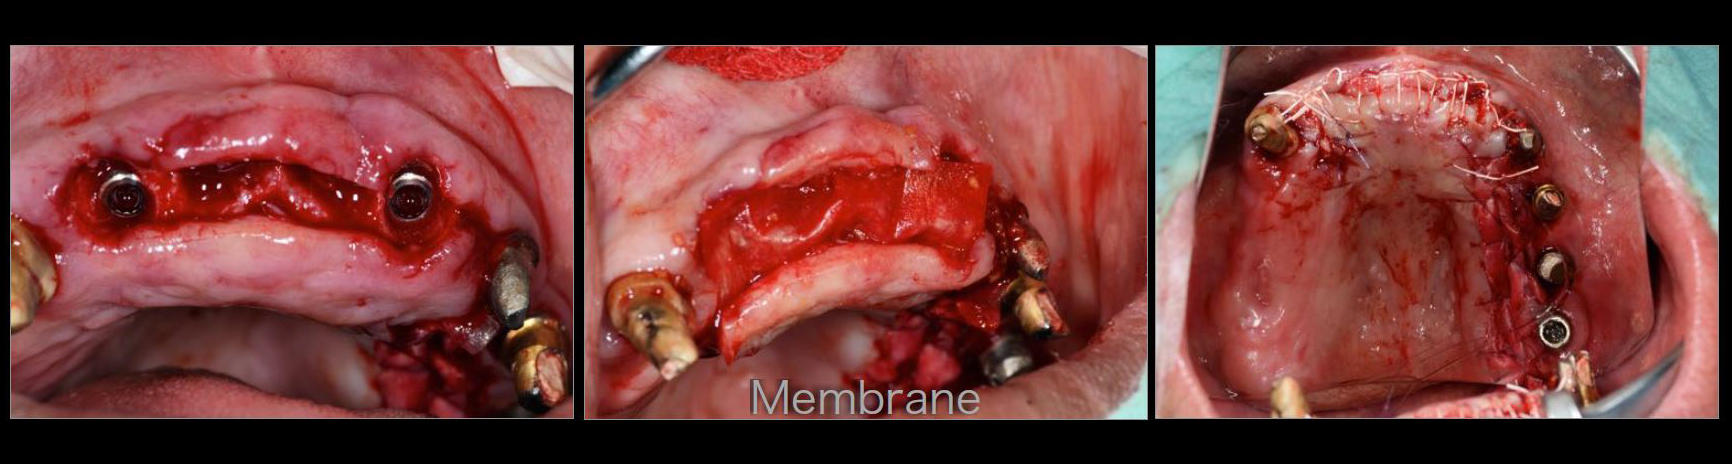

治療中02

治療中03

治療中04

治療中05

治療中06

治療中07